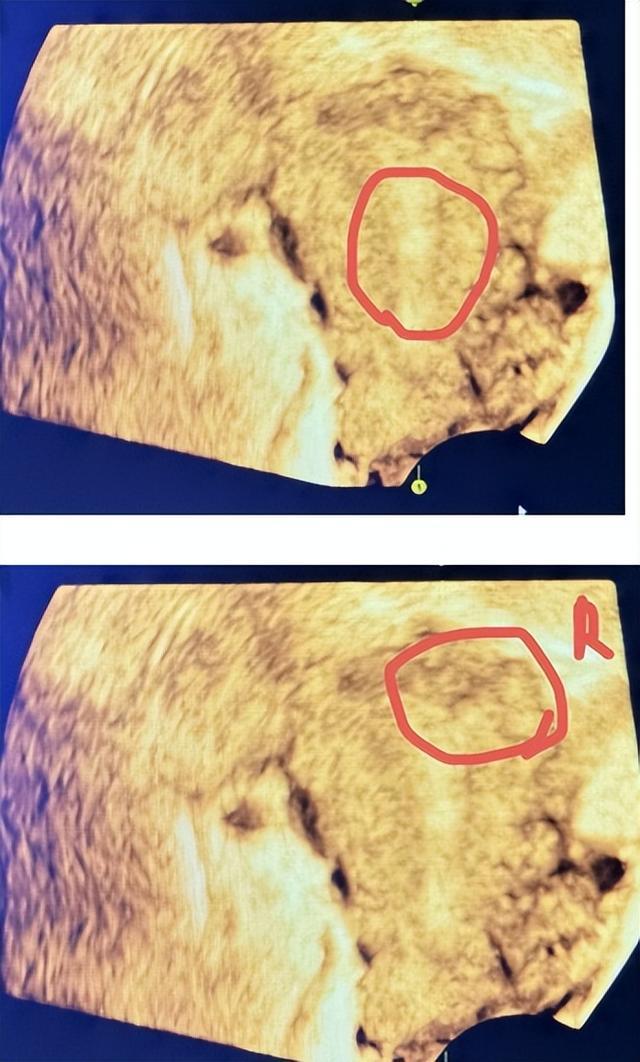

【术前超声影像资料】

34岁的曹女士,半年前曾因稽留流产行了人流术后发现自己月经量明显比以前减少。因有生育计划,曹女士来到益阳市第三人民医院妇产科就诊,B超提示子宫内膜声像改变,宫腔偏右侧宫角的位置、宫腔中段都有粘连的现象,考虑宫腔粘连可能。章媛媛医师接诊后根据曹女士症状及辅助检查结果,诊断为宫腔中度粘连。